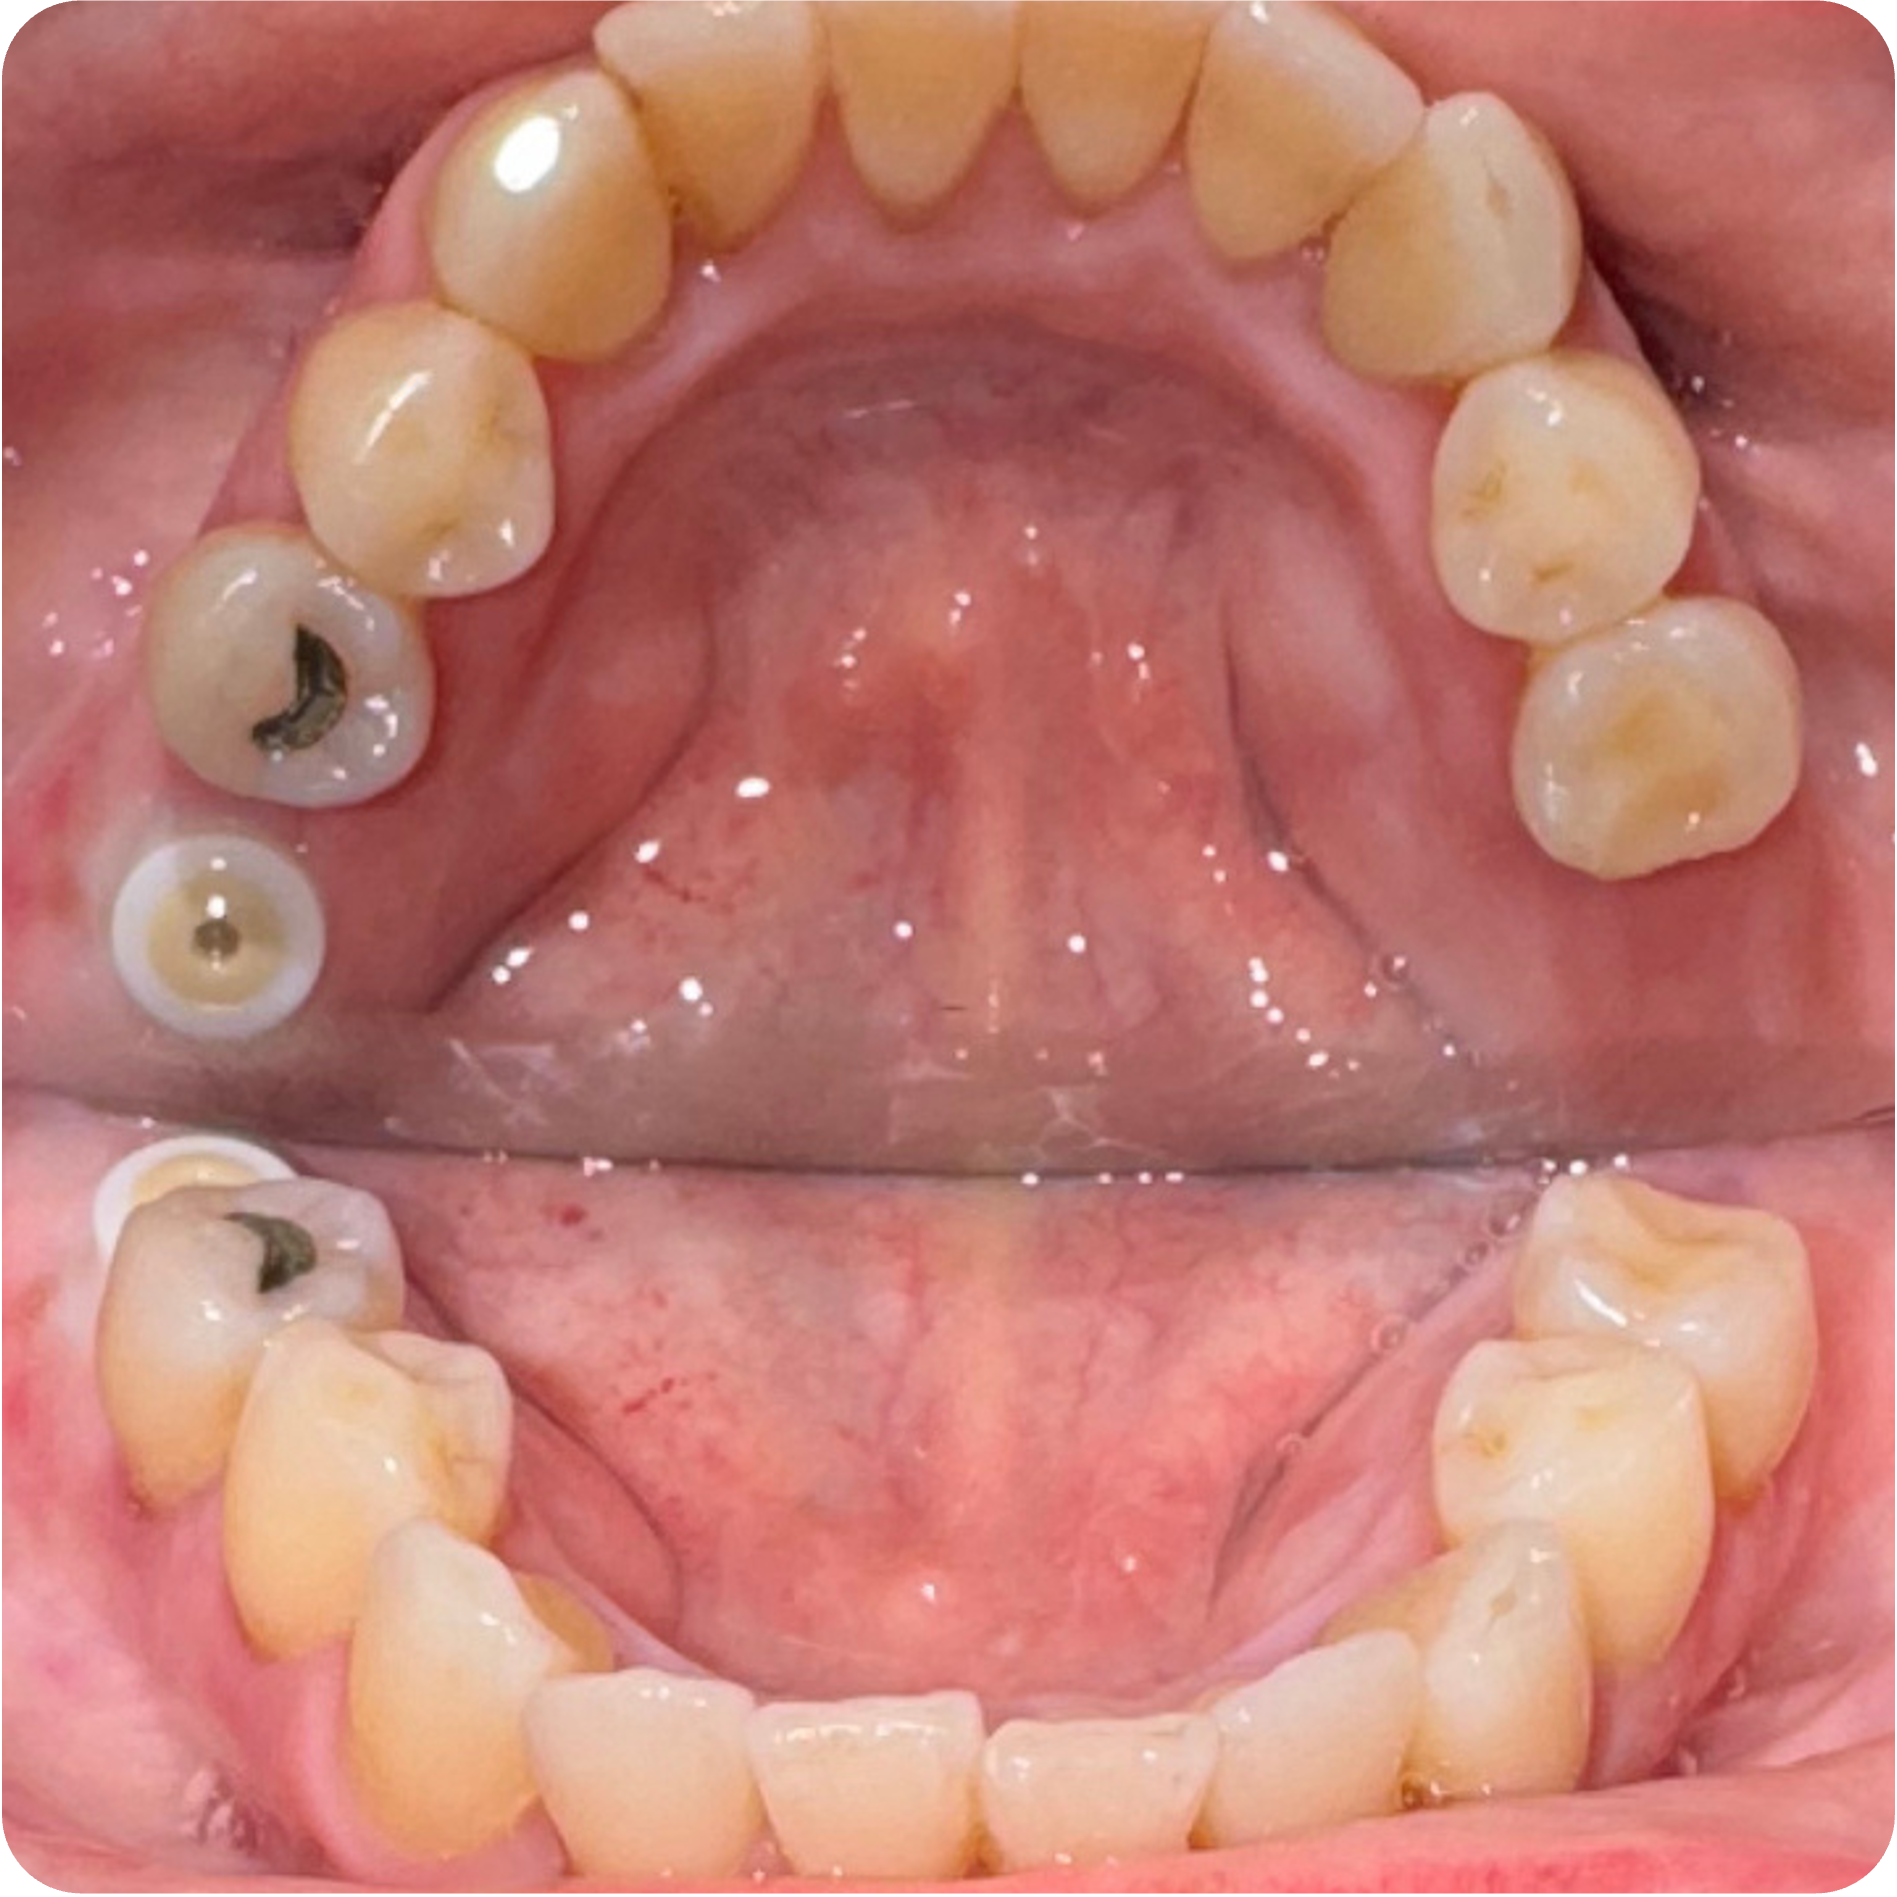

Visual Case Progression

All clinical images are shown at a consistent size for easy comparison.

Before & After (Groton Wellness Perio Protocol)

- Implant Placement in Stabilized Sites: Once infection was controlled and bone matured, implants were placed in #3, #30, #14, and #19 to restore function and long-term structural integrity.